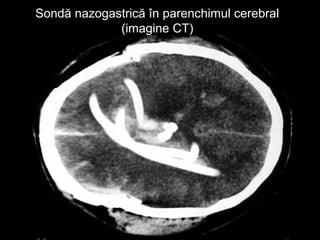

 Sondă de aspiraţie

gastrică introdusă

pe cale nazală –

manevră interzisă

Sondă nazogastrică în parenchimul cerebralSondă nazogastrică în parenchimul cerebral

(imagine CT)(imagine CT)

Hematoame periorbitaleHematoame periorbitale “Ochi de panda” – sugestivi pentru fractura de bază de craniu  Sondă de aspiraţie gastrică introdusă pe cale nazală – manevră interzisă

Sondă nazogastrică înparenchimul cerebralSondă nazogastrică în parenchimul cerebral (imagine CT)(imagine CT)